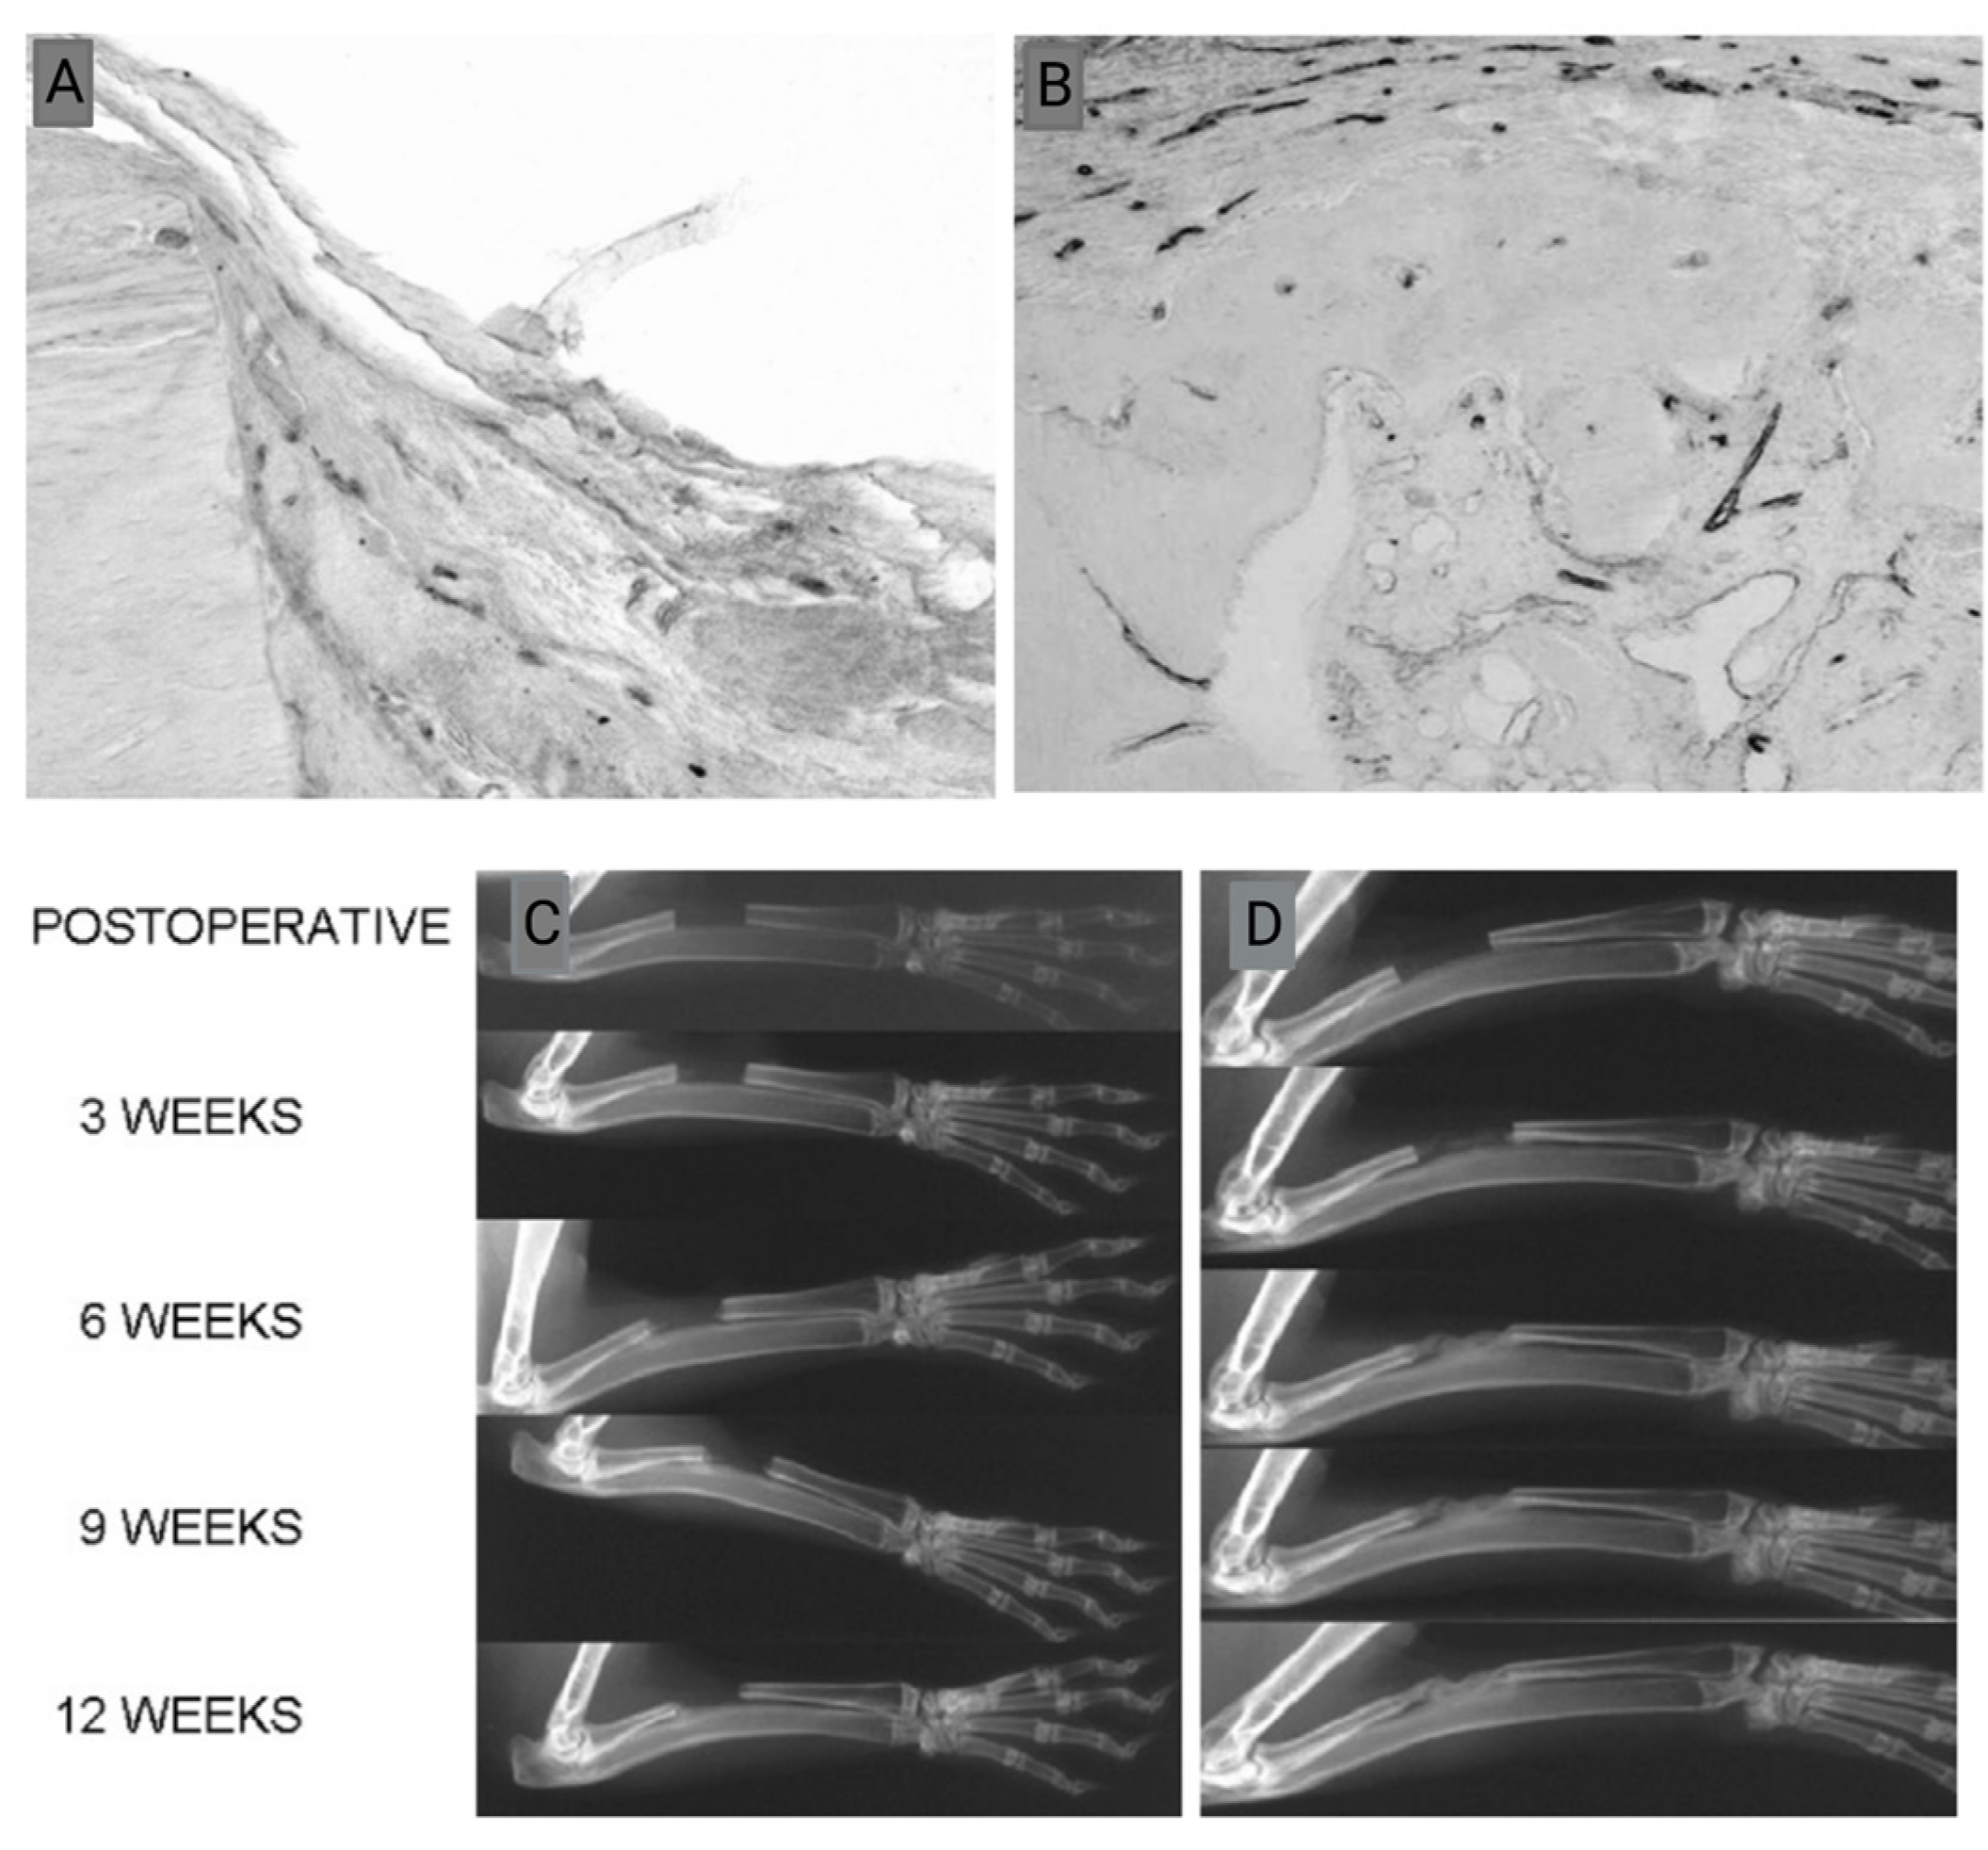

- Rabie, A.B.M.; Lu, M. Basic fibroblast growth factor up-regulates the expression of vascular endothelial growth factor during healing of allogeneic bone graft. Arch. Oral Biol. 2004, 49, 1025–1033. [Google Scholar] [CrossRef]

- Lu, M.; Rabie, A. Microarchitecture of rabbit mandibular defects grafted with intramembranous or endochondral bone shown by micro-computed tomography. Br. J. Oral Maxillofac. Surg. 2003, 41, 385–391. [Google Scholar] [CrossRef] [PubMed]